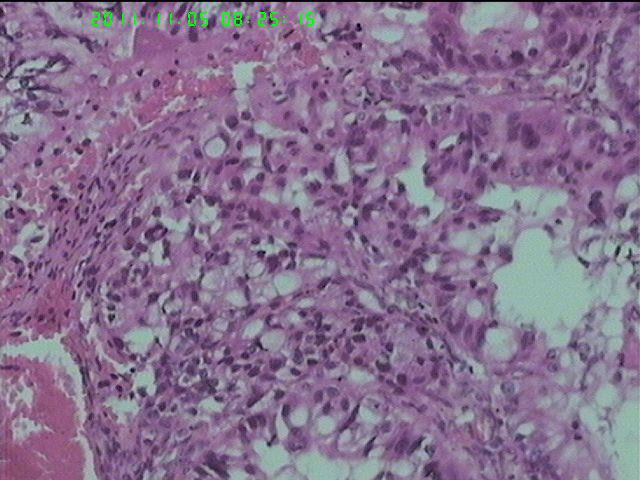

37岁女性患者,左卵巢肿块术中快速:恶性。术后左卵巢囊实性肿块14*9*5CM,灰黄色,部分乳头状,粘液样外观;子宫内膜厚1.5CM;网膜见多个小结节。图1--14左卵巢  15-19网膜  20--23宫腔

粘液腺癌(部分呈低分化)

在图中有明确浸润吗?好像看不出来,但是网膜显示非侵袭性。宫腔图片没有显示浸润。请多上边缘处图像。

请临床查有无阑尾病变,排除阑尾肿瘤转移后,如果没有明确浸润,倾向粘液性*交界性肿瘤伴腹膜种植,肠型。

总之先排除阑尾来源,再看有无浸润,有浸润才打癌。

卵巢粘液性囊腺癌伴内膜及网膜转移。

图1、4、5、6、11中可见疏松组织,网状结构,并见可疑透明小体,加上患者年纪较年轻,卵黄囊瘤不能除外,粘液腺结构可能是卵黄囊中的内胚层成分。且形态上与网膜结节相似。